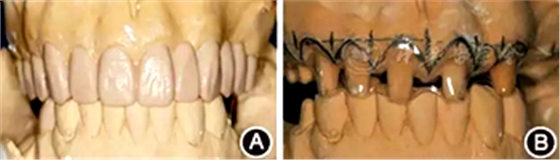

口腔衛(wèi)生狀況一般,菌斑指數(shù)0~2,鄰面少量軟垢;牙齦齦緣鮮紅、水腫、質軟,出血指數(shù)2~3,余牙牙齦輕度水腫,出血指數(shù)0~2;全口探診深度2~3 mm,個別位點探診深度達4~5 mm,鄰面可探及附著喪失;未查及牙齒松動及根分叉病變;烤瓷固定橋修復,冠邊緣密合度欠佳,位于齦下1~2 mm;、唇側崩瓷,邊緣暴露;上前牙牙齦線不協(xié)調(diào);缺失,右下后牙可摘局部義齒修復,固定橋修復;近中面銀汞充填,近中懸突及繼發(fā)齲;上前牙覆蓋下前牙牙冠的1/2~2/3(圖1)。

圖1 患者初診時臨床照片 A:正面微笑像;B:正面口內(nèi)像